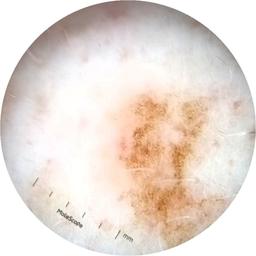

ISIC_3754278

diagnosis_1 Benign

diagnosis_confirm_type single image expert consensus

image_type dermoscopic